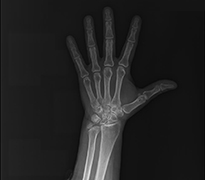

Parmak Eklemlerinde Kireçlenmeler

Başparmak Kök Eklem Kireçlenmesi (1.cmc Eklem Artrozu)